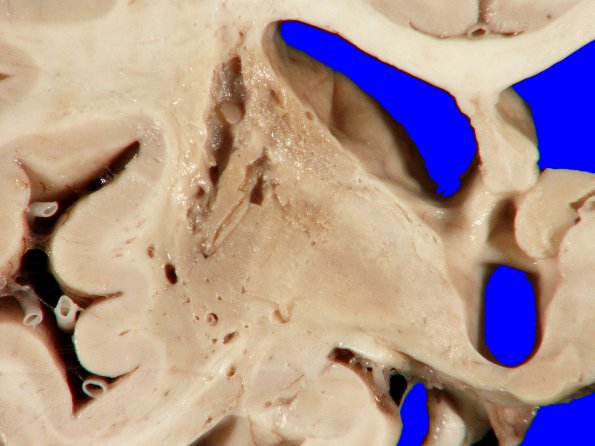

The location of this lesion in the internal capsule may have resulted in more effect than a subcortical lesion elsewhere.